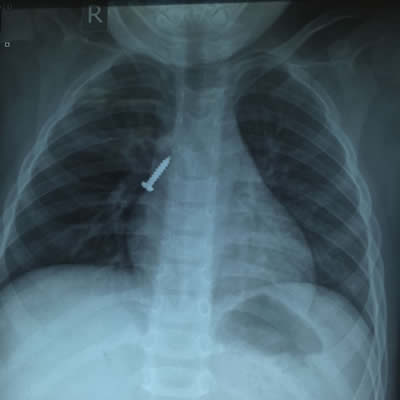

螺丝钉卡在宝宝气管 CT显示螺丝钉卡在右主支气管

手术医生把纤细的气管镜,深入宝宝喉部,看到右侧支气管中段有一金属的螺丝钉,尖端朝上,头端朝下。螺丝钉周围已经有脓性分泌物。在大家的配合下,仅5分钟,就顺利夹出了螺丝钉。螺丝钉足足有2.5厘米长,0.4厘米宽。

八位医生护士为手术保驾护航 取出来的螺丝钉长2.5厘米,粗0.4厘米